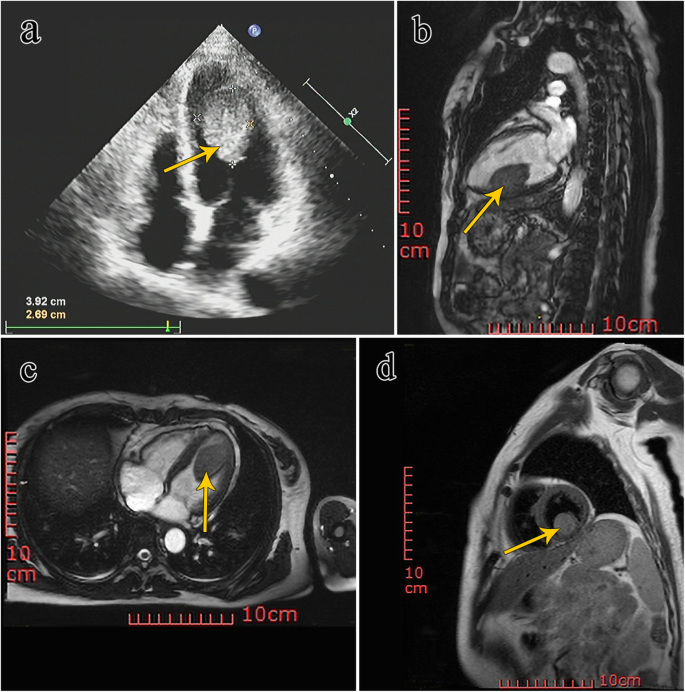

A 51-year-old female, who had been complaining of intermittent diarrhea for the previous 2 years, was admitted to our hospital with recurrent watery diarrhea along with abdominal pain for 3 days. The patient had received intermittent treatment of anti-inflammatory drugs and symptomatic treatment for 2 years due to recurrent diarrhea. However, the treatment was not effective and she had lost 5 kg body weight. To determine the specific cause of weight loss and recurrence of diarrhea, the doctor examined the patient thoroughly. No abnormality was evident in gastroscopy and proctoscopy. Enhancement of total abdominal computed tomography (CT) scan suggested a suspected space occupation in the left ventricle. Echocardiography indicated a 45 mm × 28 mm mass in the left ventricle, and a malignant tumor was suspected (Fig. 1a). Magnetic resonance imaging (MRI) was performed to confirm the diagnosis; the image showed an oval mass measuring 28 cm × 26 cm × 41 cm in the inferior wall of the left ventricle with unclear boundary and limited movement, and equal T1 and long T2 signals (Fig. 1b, c, d), and a myxoma was suspected. All the indexes of myocardial enzymes were normal. The urine metabolites were normal with exception of slightly elevated calcium levels (2.68 mmol/L, normal reference range: 2.20–2.65 mmol/L) and slightly elevated phosphorus levels (1.95 mmol/L, 0.81–1.45 mmol/L). The patient was transferred from the Department of Gastroenterology to that of Cardiac Surgery for surgical tumor resection.